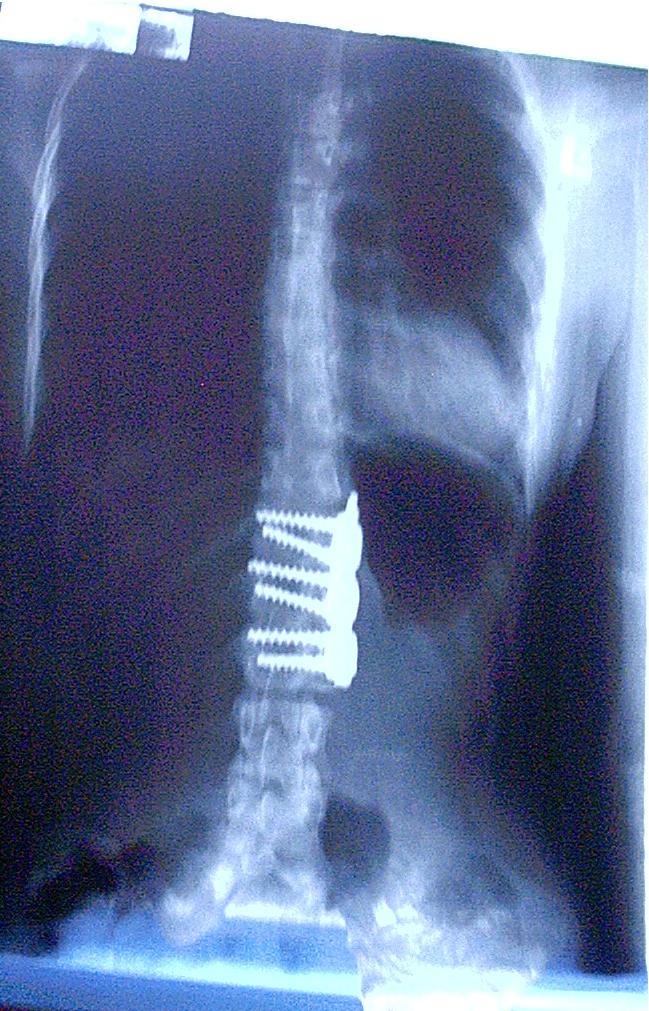

Interestingly David Hanscom, MD wrote a piece on why he is STOPPING spine surgery (please read). There is growing data that success of spine surgery is horrible (like less than 50%). To the degree that outside of the reasons I wrote above- it should never be done.  A review study by Epstein in 2011, noted 17% of spinal surgeries from one particular neurosurgeon were unnecessary. Yes, this is 1 surgeon but if we extrapolate the data, the numbers become staggering. Between 1998-2008 the cost for spinal fusions in the US rose 690% to the tune of about $100K per surgery (and nearly a half million performed) which equals over 50 Billion dollars.

But are there reasons for spine surgery? Yes, but this list is going to be small. 1) A person develops new onset of bowel or bladder issues in conjunction with their back pain 2) An individual loses the ability to control their leg/foot 3) Some kind of major trauma resulting in true instability (a fracture) of the spine- not too common 4) Secondary issue as a result of treatment for cancer.

Outside of these reasons, surgery is NOT NECESSARY and NOT ADVISED AT ALL. This is not to ignore pain or inability to live the way a person wants. This just means surgery is not the answer, something else is.